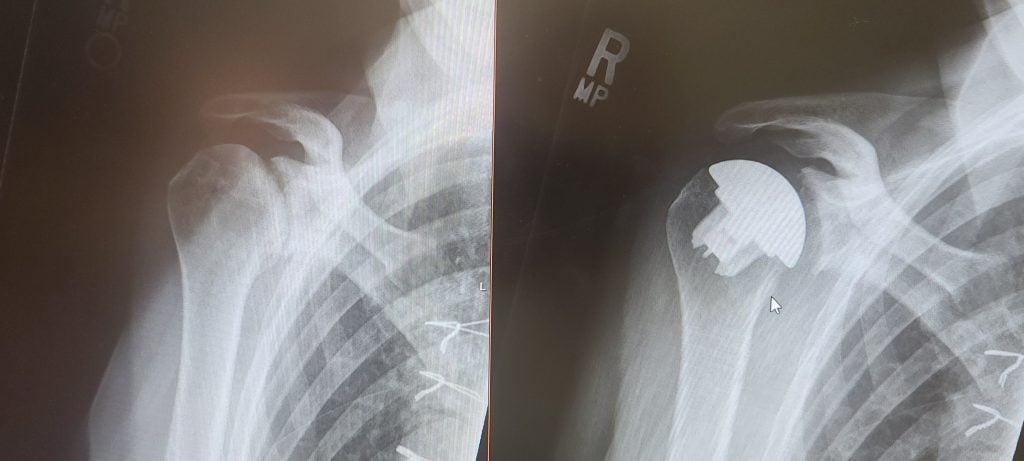

Reverse Shoulder Replacement

Reverse Total Shoulder Replacement Puts 70 Year Old Back in the Game!

We discussed the post-surgical pros and cons of an anatomic vs. reverse total shoulder replacement and Dr. Gulotta wasn’t at all fazed by my two-page spreadsheet of questions. His concern was making sure that I was informed and comfortable; which reassured me that I would be in good hands -- both figuratively and literally!!!  The final decision (which he made during surgery) was that I needed a Reverse Total Shoulder Replacement. The actual surgery was amazing: from check-in through discharge. The anesthesiology team met with me to discuss my concerns, the Anesthesia Pain Management team made sure that any post-op pain was well managed, and the nursing team was wonderful.